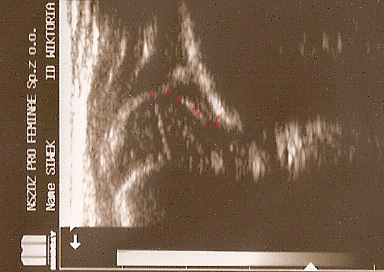

Typ IIc czerwone kropki od lewej) pokazują punkty do kreślenia 1 środek geometryczny obrąbka 2.brzeg kostny(dwa punkty);3.gałąż dolną kości biodrowej